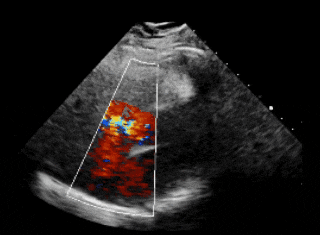

术前超声

超声下可见左盘面贴靠主动脉侧

超声下可见双盘面骑跨